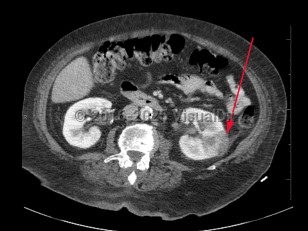

Imaging Studies image of Pyelonephritis - imageId=8360960. Click to open in gallery.  caption: '<span>Axial image from contrast enhanced CT scan demonstrating a peripheral, wedge-shaped, low attenuation region in the left kidney, consistent with pyelonephritis with possible abscess.</span>'

Axial image from contrast enhanced CT scan demonstrating a peripheral, wedge-shaped, low attenuation region in the left kidney, consistent with pyelonephritis with possible abscess.